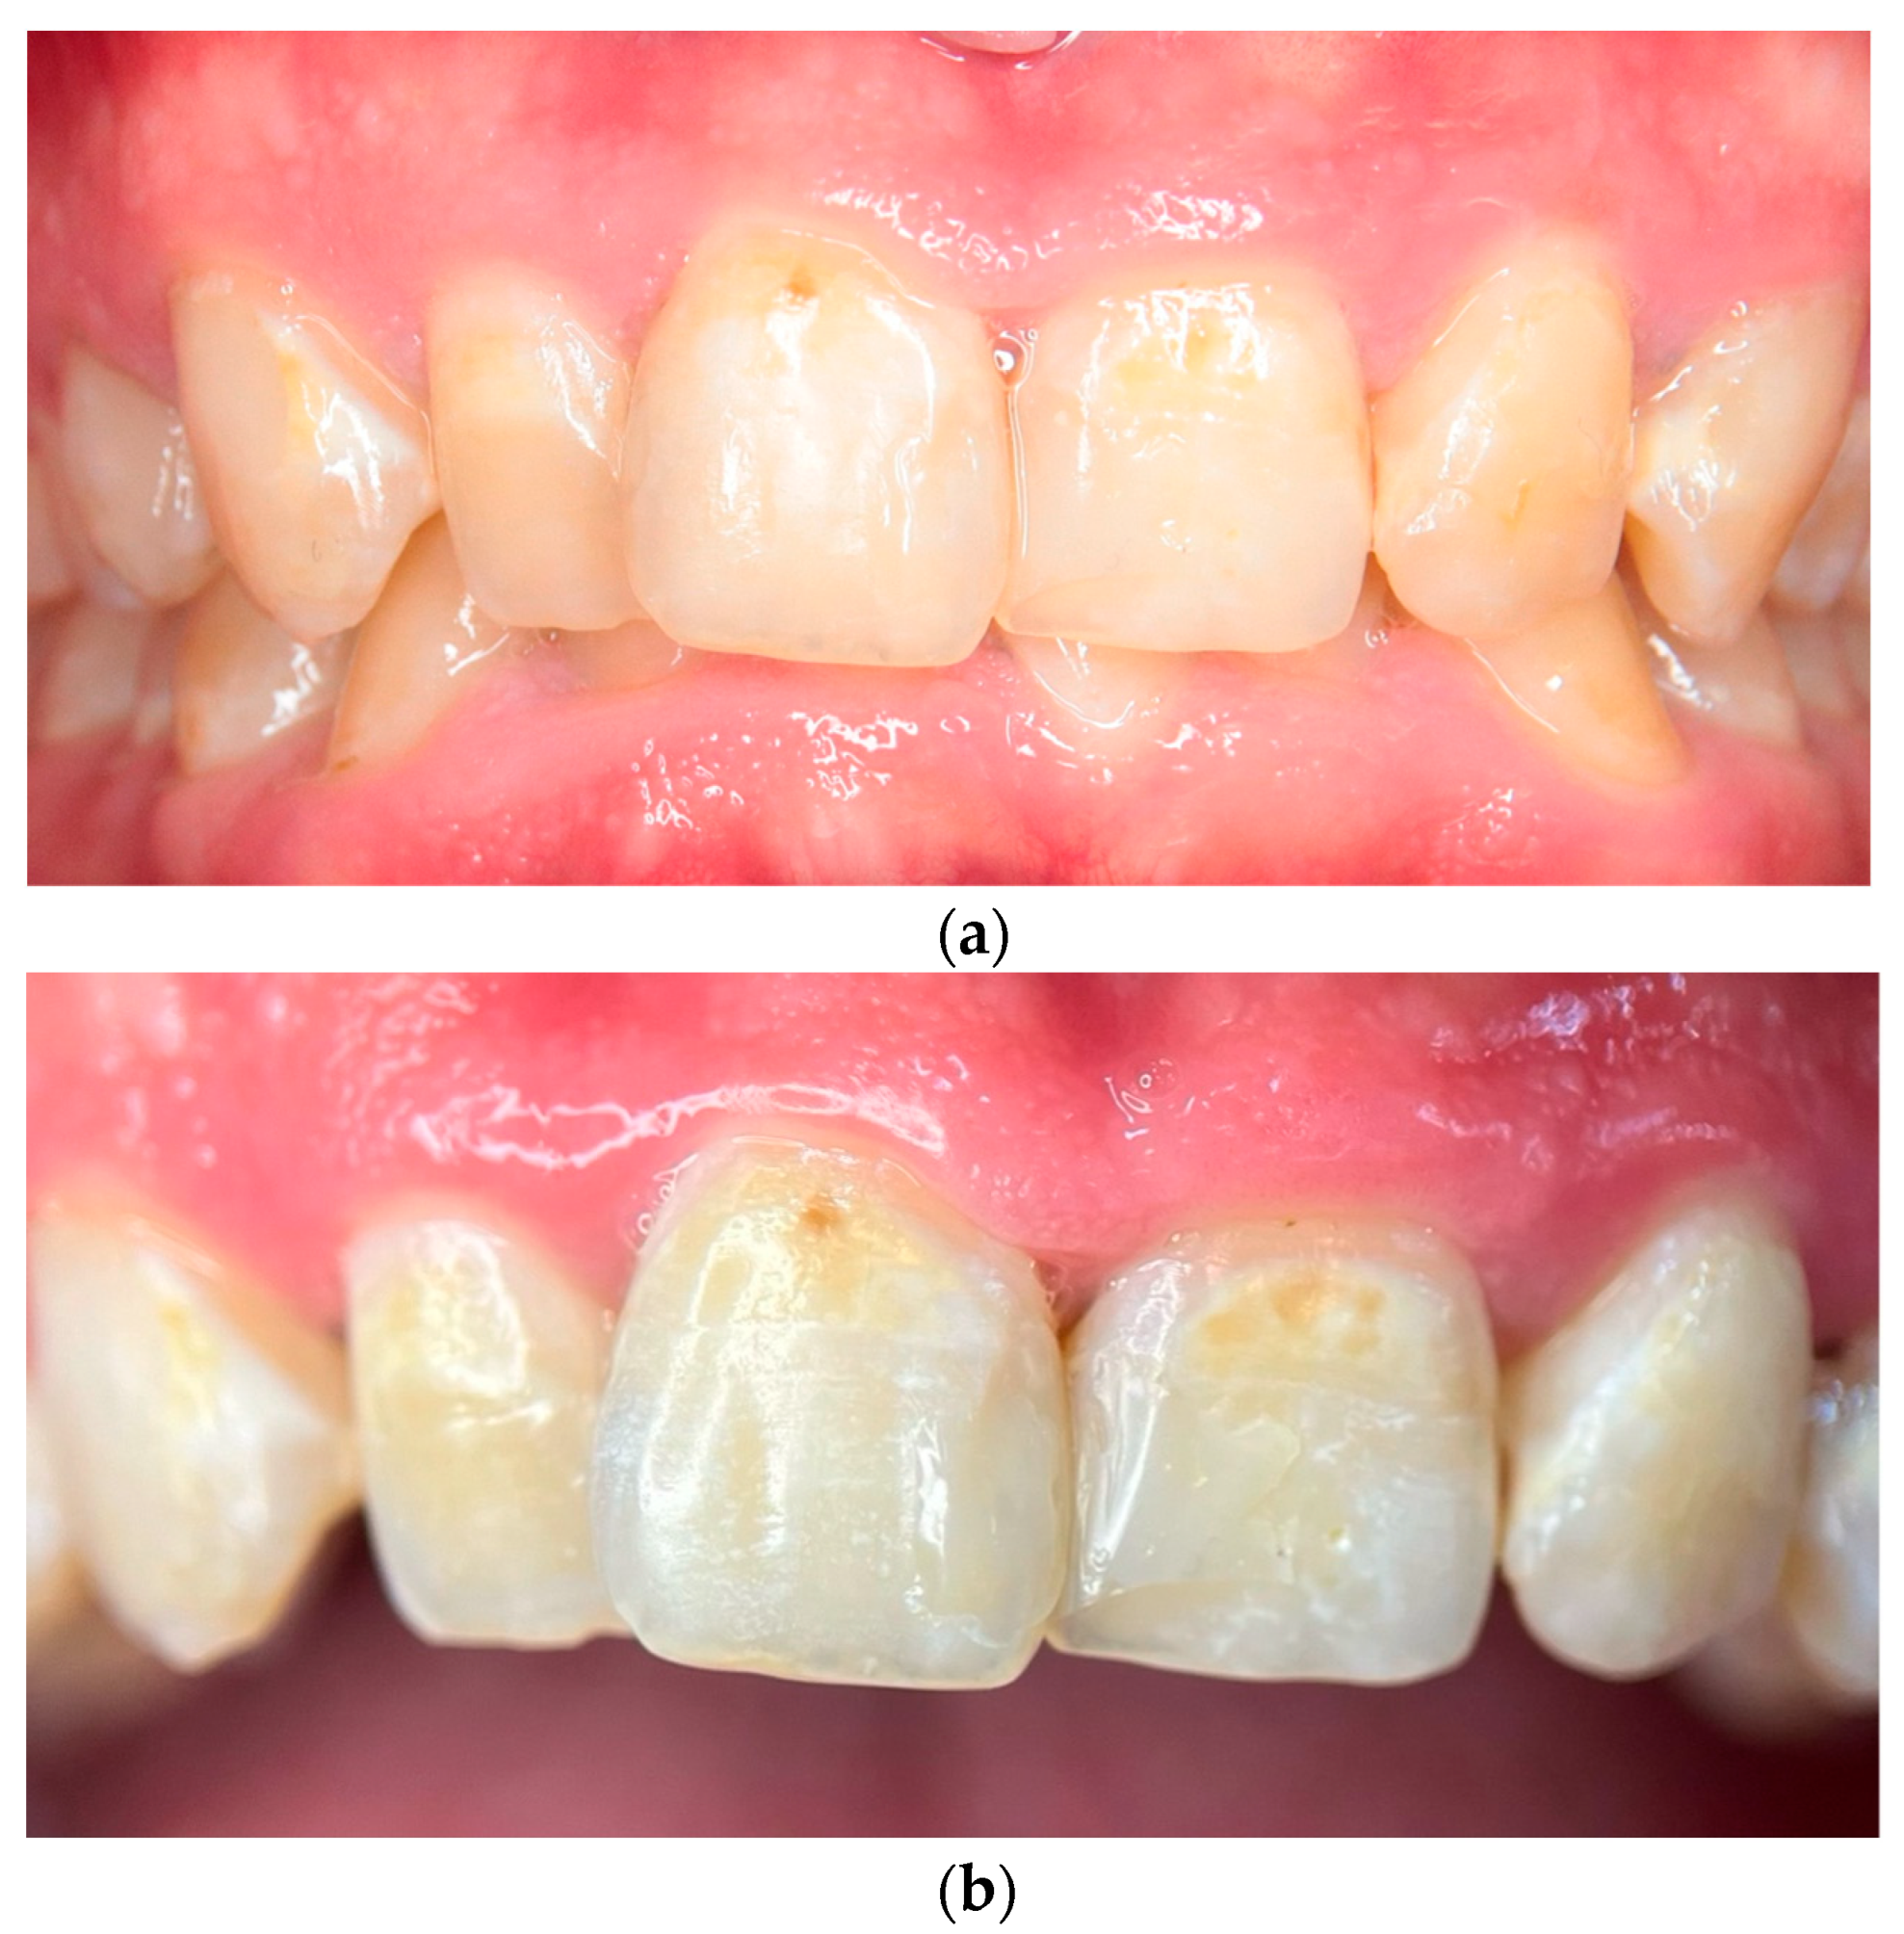

To comprehensively document the patient’s condition and evaluate the effectiveness of remineralization therapy, intraoral photographs at baseline and at 120-day follow-up and photometric analyses were performed. At the initial visit (Day 0), clinical examination revealed extensive demineralization affecting all tooth surfaces, particularly the anterior teeth, along with the presence of a deep overbite and signs of gingivitis, including localized inflammation and bleeding upon probing (Figure 1a). A high-resolution macro photograph was taken providing a detailed close-up of the central incisors at baseline, highlighting specific areas of demineralization and discoloration. Standardization was achieved using a 100 mm macro lens and a mini tripod, maintaining a constant shooting distance of 0.3 m from the patient. The image was captured under controlled lighting conditions. The tooth surface was documented in a dry state to enhance the visibility of demineralization patterns (Figure 1b).

Figure 1.

(a) Intraoral photograph at baseline (Day 0) showing extensive demineralization and discoloration affecting all tooth surfaces, particularly the upper anterior teeth. The presence of a deep overbite is also evident, as well as the presence of restorations on teeth 11, 12, 21, and 22. (b) High-resolution photograph of the central incisors at baseline, highlighting severe demineralization and discoloration. The image was captured under dry conditions to enhance visibility of demineralization patterns.